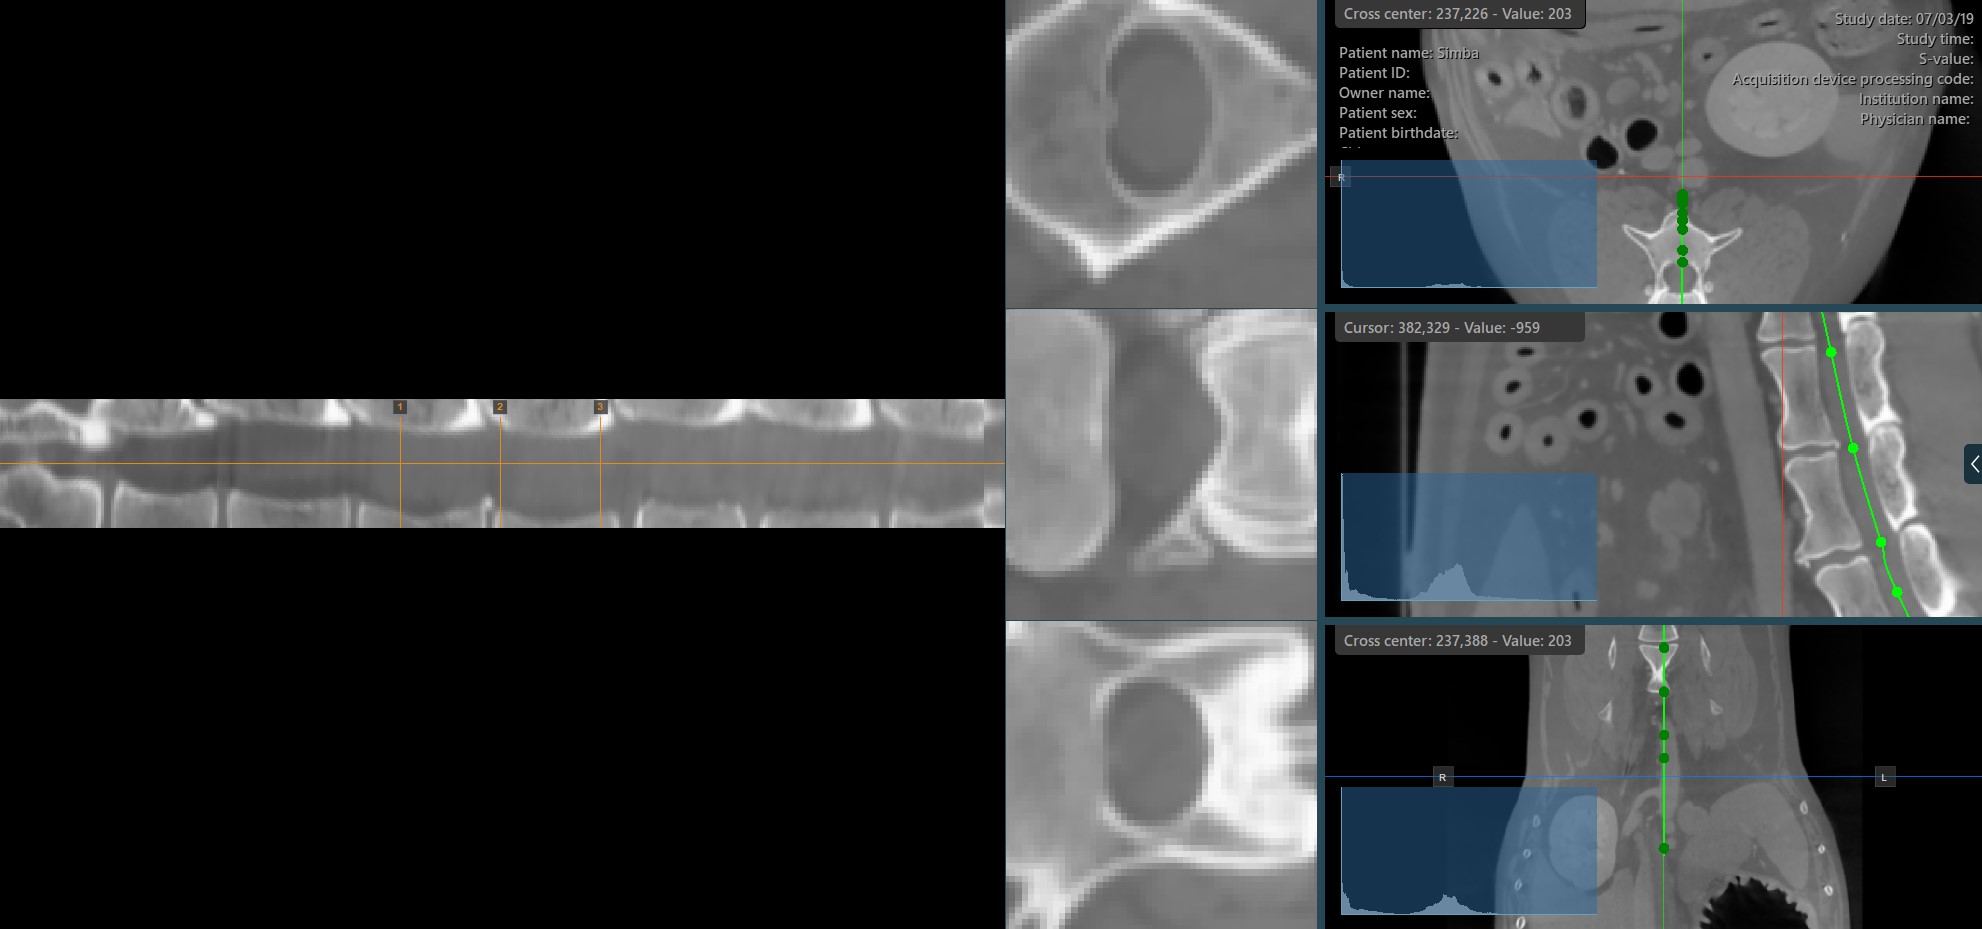

Hovering over the straightened view of the CMPR path will display an orange dot on the path drawn on the MPR images, highlighting the precise location of the cursor.

Similar to the regular MPR view, the measurement tools available in the CT Viewer can also be used on the three available CMPR slicer viewports.

Modify the CMPR path by selecting the Select/Move Item tool and assigning one of the available mouse buttons to it. Press and drag one of the base points of the path to modify its position.

Other CMPR Parameters

In addition to the options to create and delete CMPR paths, the CT Viewer offers additional parameters for better configuration of the CMPR view.

• Adjust the angle and rotate the axis of the CMPR views by dragging the slider in the appropriate direction. Press the Reset icon in the middle to reset the angle.

• Modify the position of the slicers by dragging the slider in the appropriate direction.

• Adjust the distance between the slicers by using the Slicing Width slider.

• Change the height of the slicers and the view to show a bigger portion of the CMPR view.